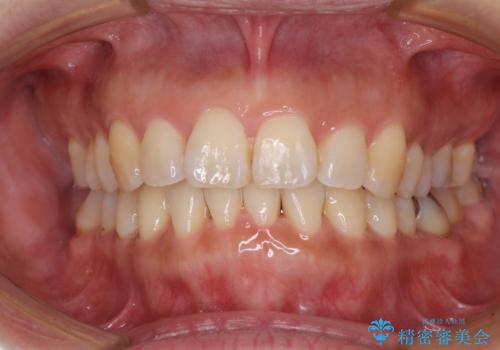

- 上下前歯の叢生を気にして来院された患者様です。

費用を抑え、期間もあまりかけずに治療をしたいとのことで、インビザライン・ライトを用いて矯正治療を行うこととしました。

インビザライン・ライトは、製作できるアライナーの枚数に制限があるため、移動可能な量に限りがあります。

一方で、半年から1年程度で治療を終えることができるため、軽度の歯列不正の患者様には大変お勧めです。